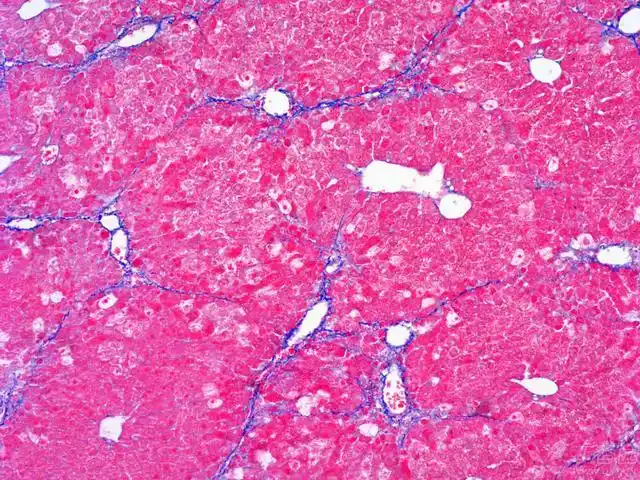

masson染色_病理染色_北京晶莱华科生物技术有限公司